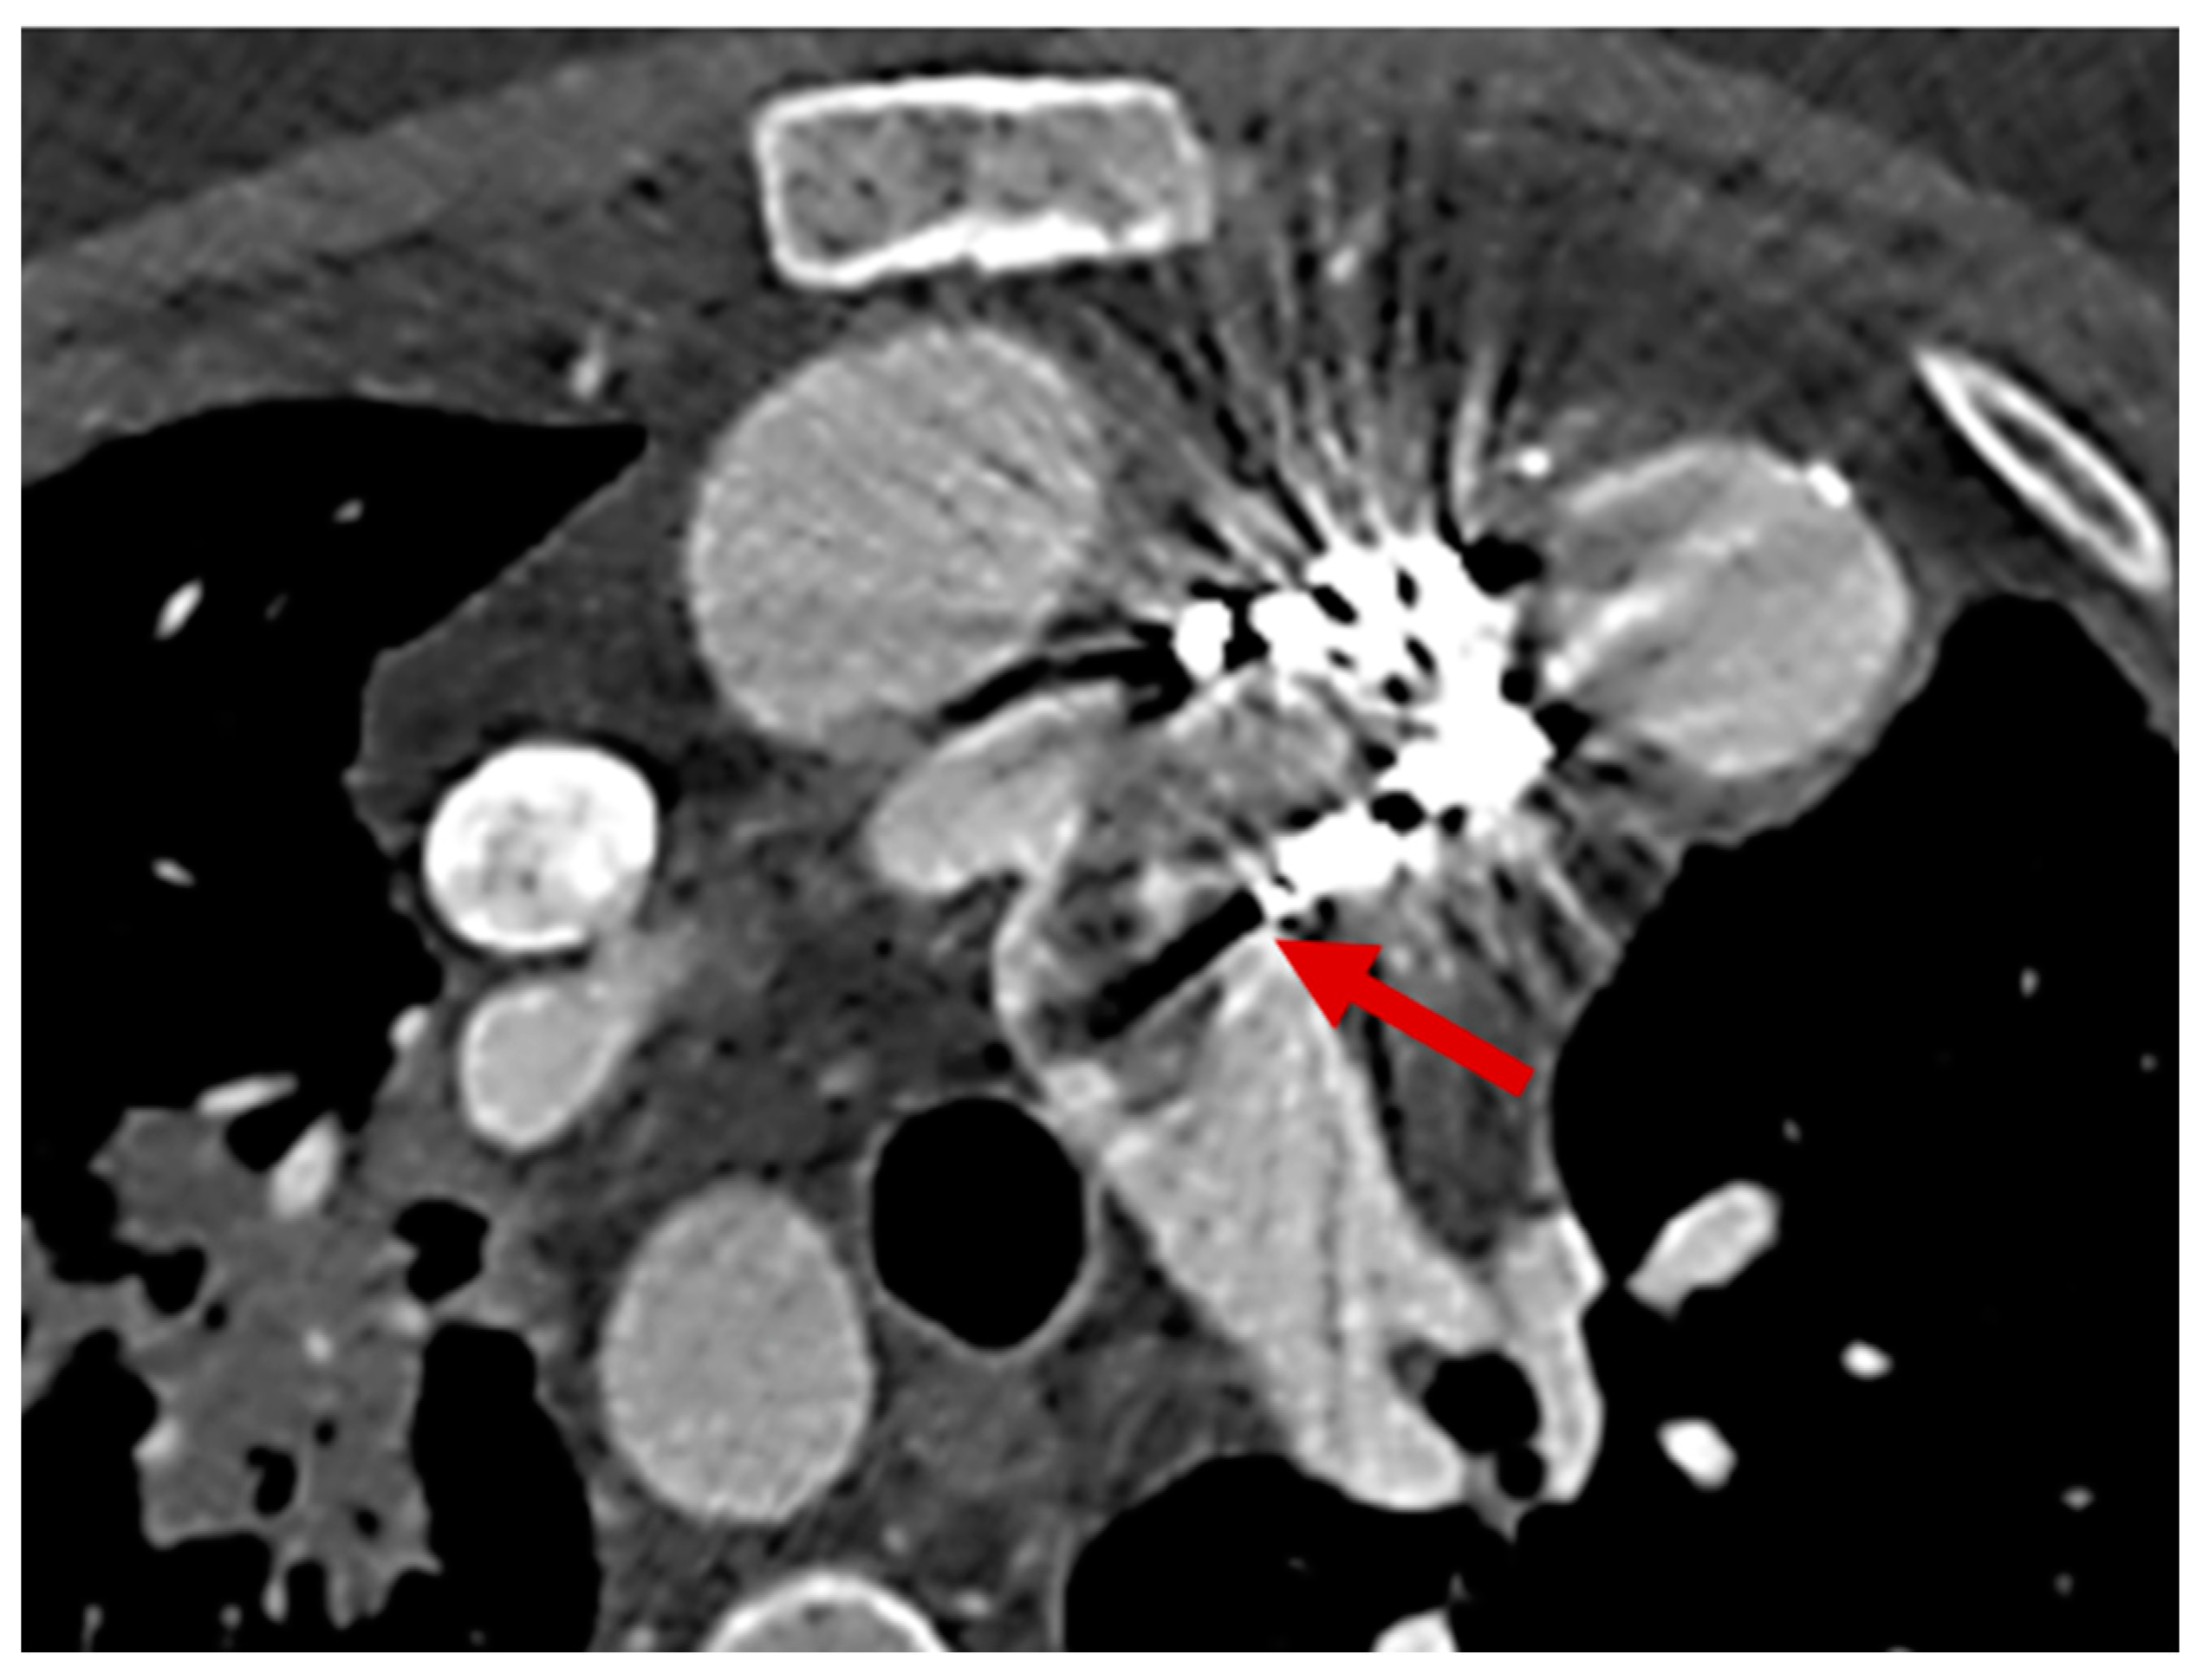

- Detecting Device-Related Infections: PET/CT is highly effective for evaluating infections involving prosthetic valves, pacemaker leads, and other intracardiac devices (Figure 7). It offers unmatched sensitivity in visualizing device pockets and lead tracks, helping differentiate sterile thrombi from infectious vegetations. This is critical in CHD patients, who frequently require surgical implants as part of their treatment.

- Integration with CT Angiography (PET/CTA): When PET is paired with CT angiography, the resulting hybrid imaging achieves remarkable diagnostic precision. This combination leverages PET’s sensitivity for detecting metabolic activity in infected tissues and CTA’s detailed visualization of structural abnormalities. For instance, PET/CTA achieves a sensitivity of 91% and a positive predictive value of 93% for diagnosing infections involving prosthetic valves and intracardiac devices, significantly enhancing diagnostic confidence [99].